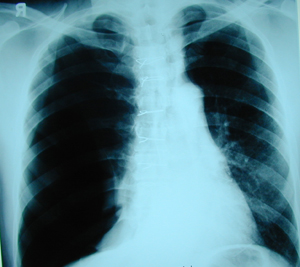

Εικόνα 1

Οπισθιοπροσθία ακτινογραφία θώρακος, που δείχνει σχεδόν oλικό πνευμοθώρακα στο δεξιό ημιθωράκιο που παρεκτοπίζει το μεσοθωράκιο προς την υγιή πλευρά.